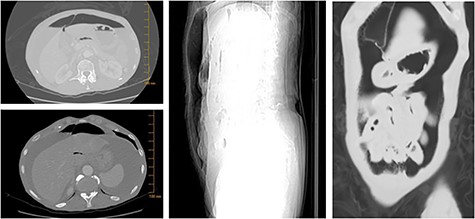

Six months later, she re-presented to the emergency department with acute onset abdominal pain, nausea and non-billous emesis. Physical examination was again significant for mild epigastric tenderness with no peritoneal signs, however imaging studies revealed free air in the abdomen (Fig. 3). The patient was diagnosed with a perforated viscus, and taken for urgent surgery. She was found to have a 4-mm duodenal perforation, which was excised and repaired with a Graham patch. Laparotomy was also significant for an umbilical hernia with fat, which was repaired primarily and contents sent to pathology for evaluation. While the hernia contents appeared grossly normal on examination, biopsy was found significant for a poorly differentiated, GATA3 and estrogen receptor (ER) positive, CDX2 negative SRCC with lobular features (Fig. 4).